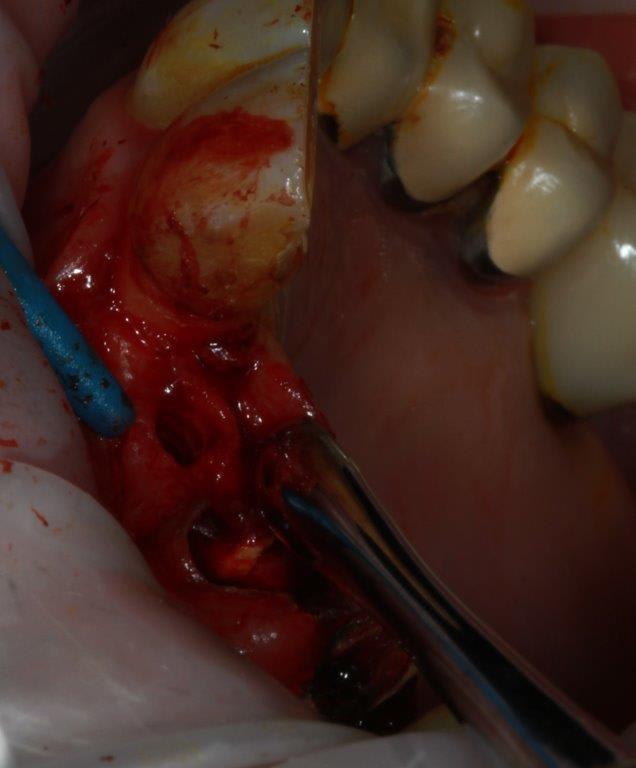

ostéotome 1mm

spreaders A/B/C/D/E après avoir scindé la crête à la lame N° 11 (sur 12 à 15mm)